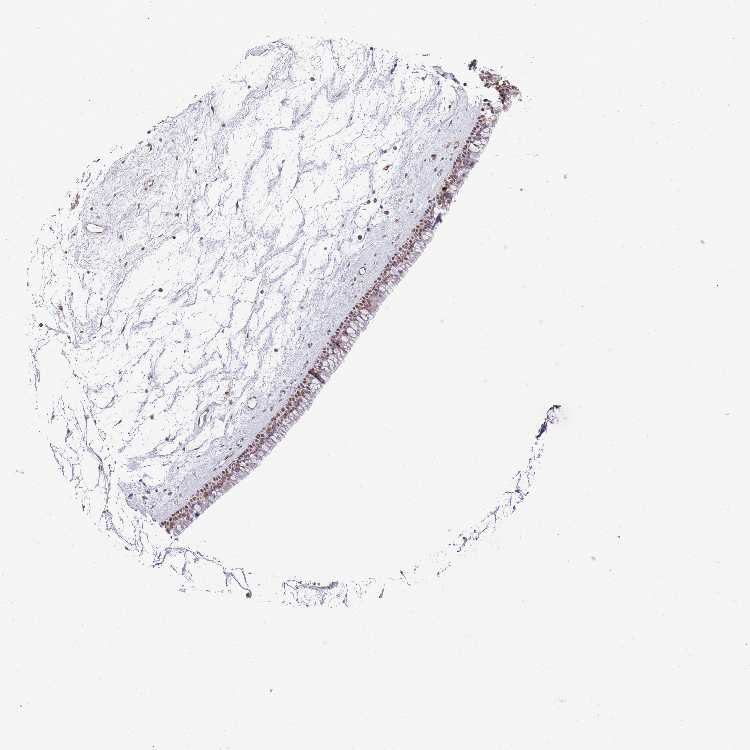

TISSUE PRIMARY DATA NASOPHARYNX Show tissue menu

NASOPHARYNX - Antibody stainingi

Antibody staining in the annotated cell types in the current human tissue is reported as not detected, low, medium, or high, based on conventional immunohistochemistry profiling in selected tissues. This score is based on the combination of the staining intensity and fraction of stained cells.

Each image is clickable and will lead to virtual microscopy that enables deeper exploration of all samples and also displays staining intensity scores, fraction scores and subcellular localization as well as patient and tissue information for each sample.

Antibody HPA039634Antibody HPA048127

Respiratory epithelial cells MediumMedium